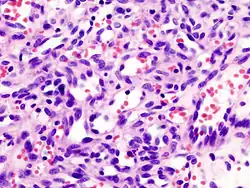

Mikro: Proliferation der Intima und fibrinoide Nekrose

Makro: Hauptsächlich die kleinen bis mittelgroßen Arterien sind betroffen. Es kommt zur Ausbildung perlschnurartig angeordneter kleiner Knötchen

Mikro: Endothelproliferation, Zerstörung der Elastica interna, Auftreten mehrkerniger Riesenzellen.

Mikro: Unspezifische Entzündung der Media, Riesenzellen